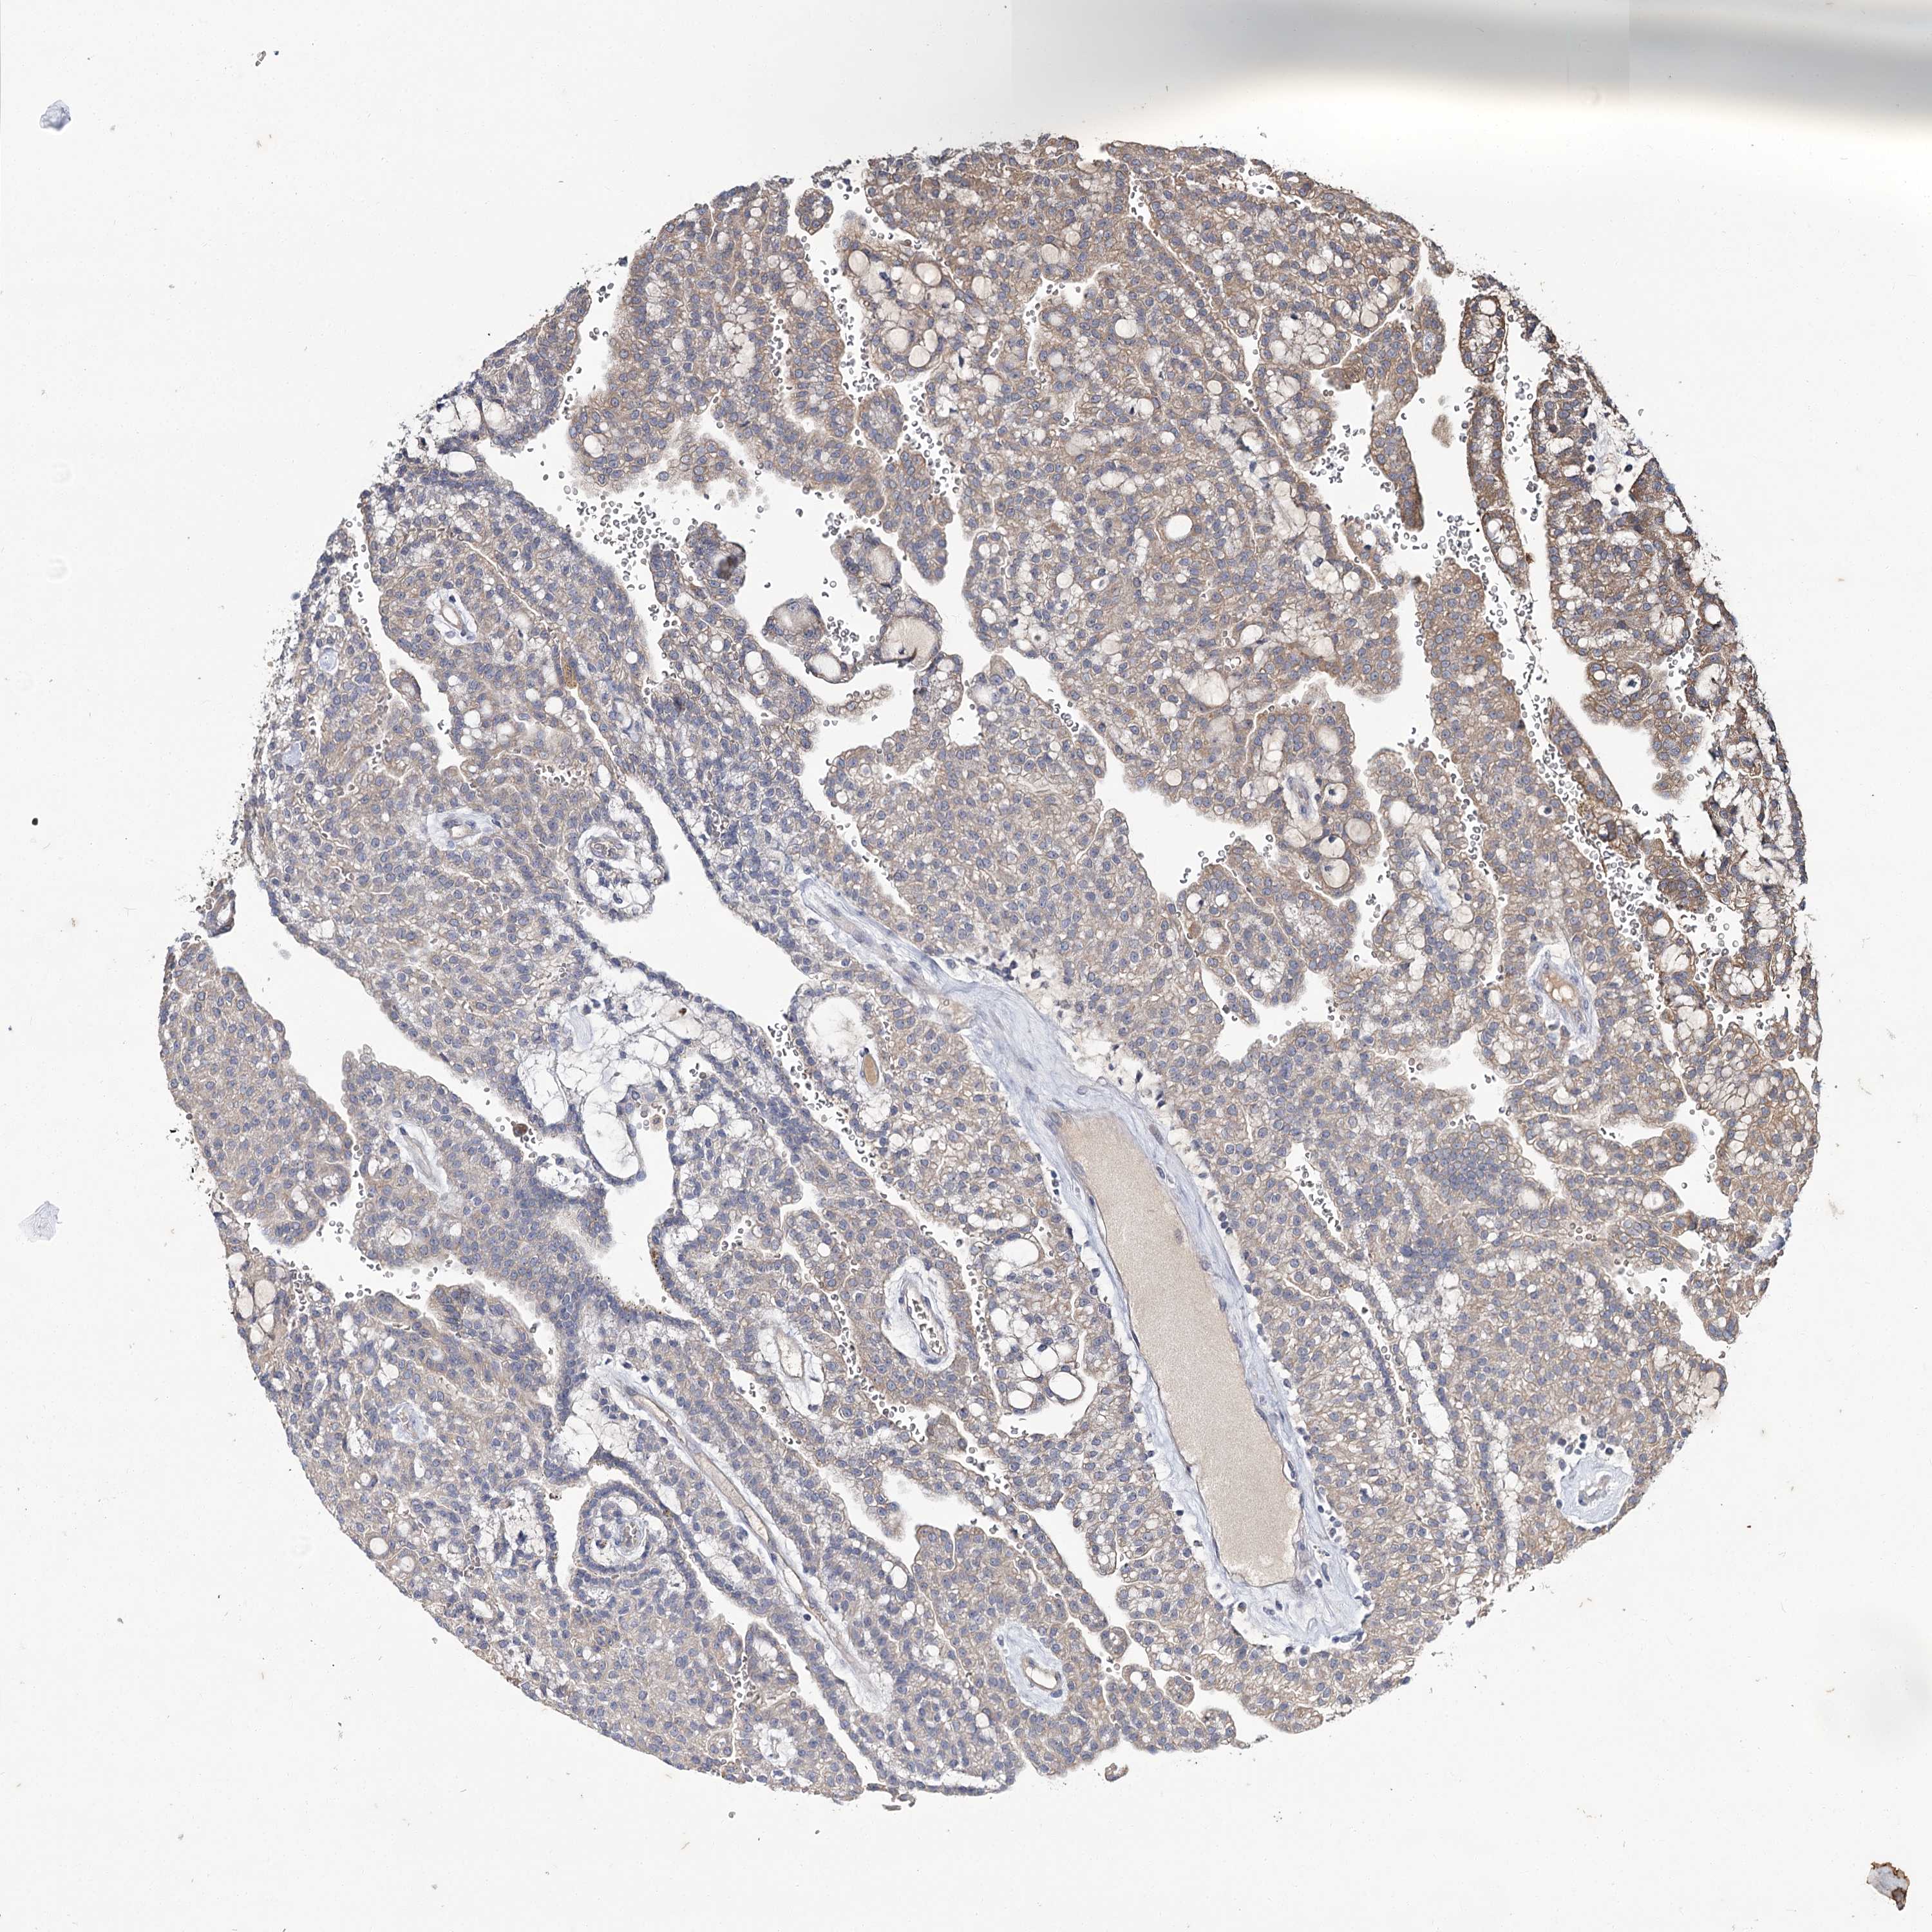

KIDNEY RENAL PAPILLARY CELL CARCINOMA (TCGA) - Interactive survival scatter ploti

The Survival Scatter plot shows the clinical status (i.e. dead or alive) for all individuals in the patient cohort, based on the same data that underlies the corresponding Kaplan-Meier plots. Patients that are alive at last time for follow-up are shown in blue and patients who have died during the study are shown in red.

The x-axis shows the expression levels (FPKM) of the investigated gene in the tumor tissue at the time of diagnosis. The y-axis shows the follow-up time after diagnosis (years). Both axes are complimented with kernel density curves demonstrating the data density over the axes. The top density plot shows the expression levels (FPKM) distribution among dead (red) and alive patients (blue). The right density plot shows the data density of the survived years of dead patients with high and low expression levels respectively, stratified using the cutoff indicated by the vertical dashed line through the Survival Scatter plot. This cutoff is automatically defined based on the FPKM cutoff that minimizes the p-score. The cutoff can be changed by dragging the vertical line or by entering a cutoff value in the square labeled "Current cut-off".

Under the Survival Scatter plot the p-score landscape (black curve; left axis) is shown together with dead median separation (red curve; right axis). Dead median separation is the difference in median mRNA expression between patients who have died with high and low expression, respectively. It is calculated as follows: median FPKM expression of dead patients with high expression - median FPKM expression of dead patients with low expression. This is intended to aid the user in visually exploring custom cutoffs and the associated p-scores and dead median separation.

Individual patient data is displayed and can be filtered by clicking on one or more of the category buttons on the top of the page. Categories describing expression level and patient information include: high, low, alive, dead, female, male and tumor stages. The scale of the x-axis can be toggled between linear and log-scale by clicking on the "x log" button. Mouse-over function shows TCGA ID, patient information and mRNA expression (FPKM) for each patient.

& Survival analysisi

Kaplan-Meier plots summarize results from analysis of correlation between mRNA expression level and patient survival. Patients were divided based on level of expression into one of the two groups "low" (under cut off) or "high" (over cut off). X-axis shows time for survival (years) and y-axis shows the probability of survival, where 1.0 corresponds to 100 percent.

MFN1 is not prognostic in Kidney Renal Papillary Cell Carcinoma (TCGA)